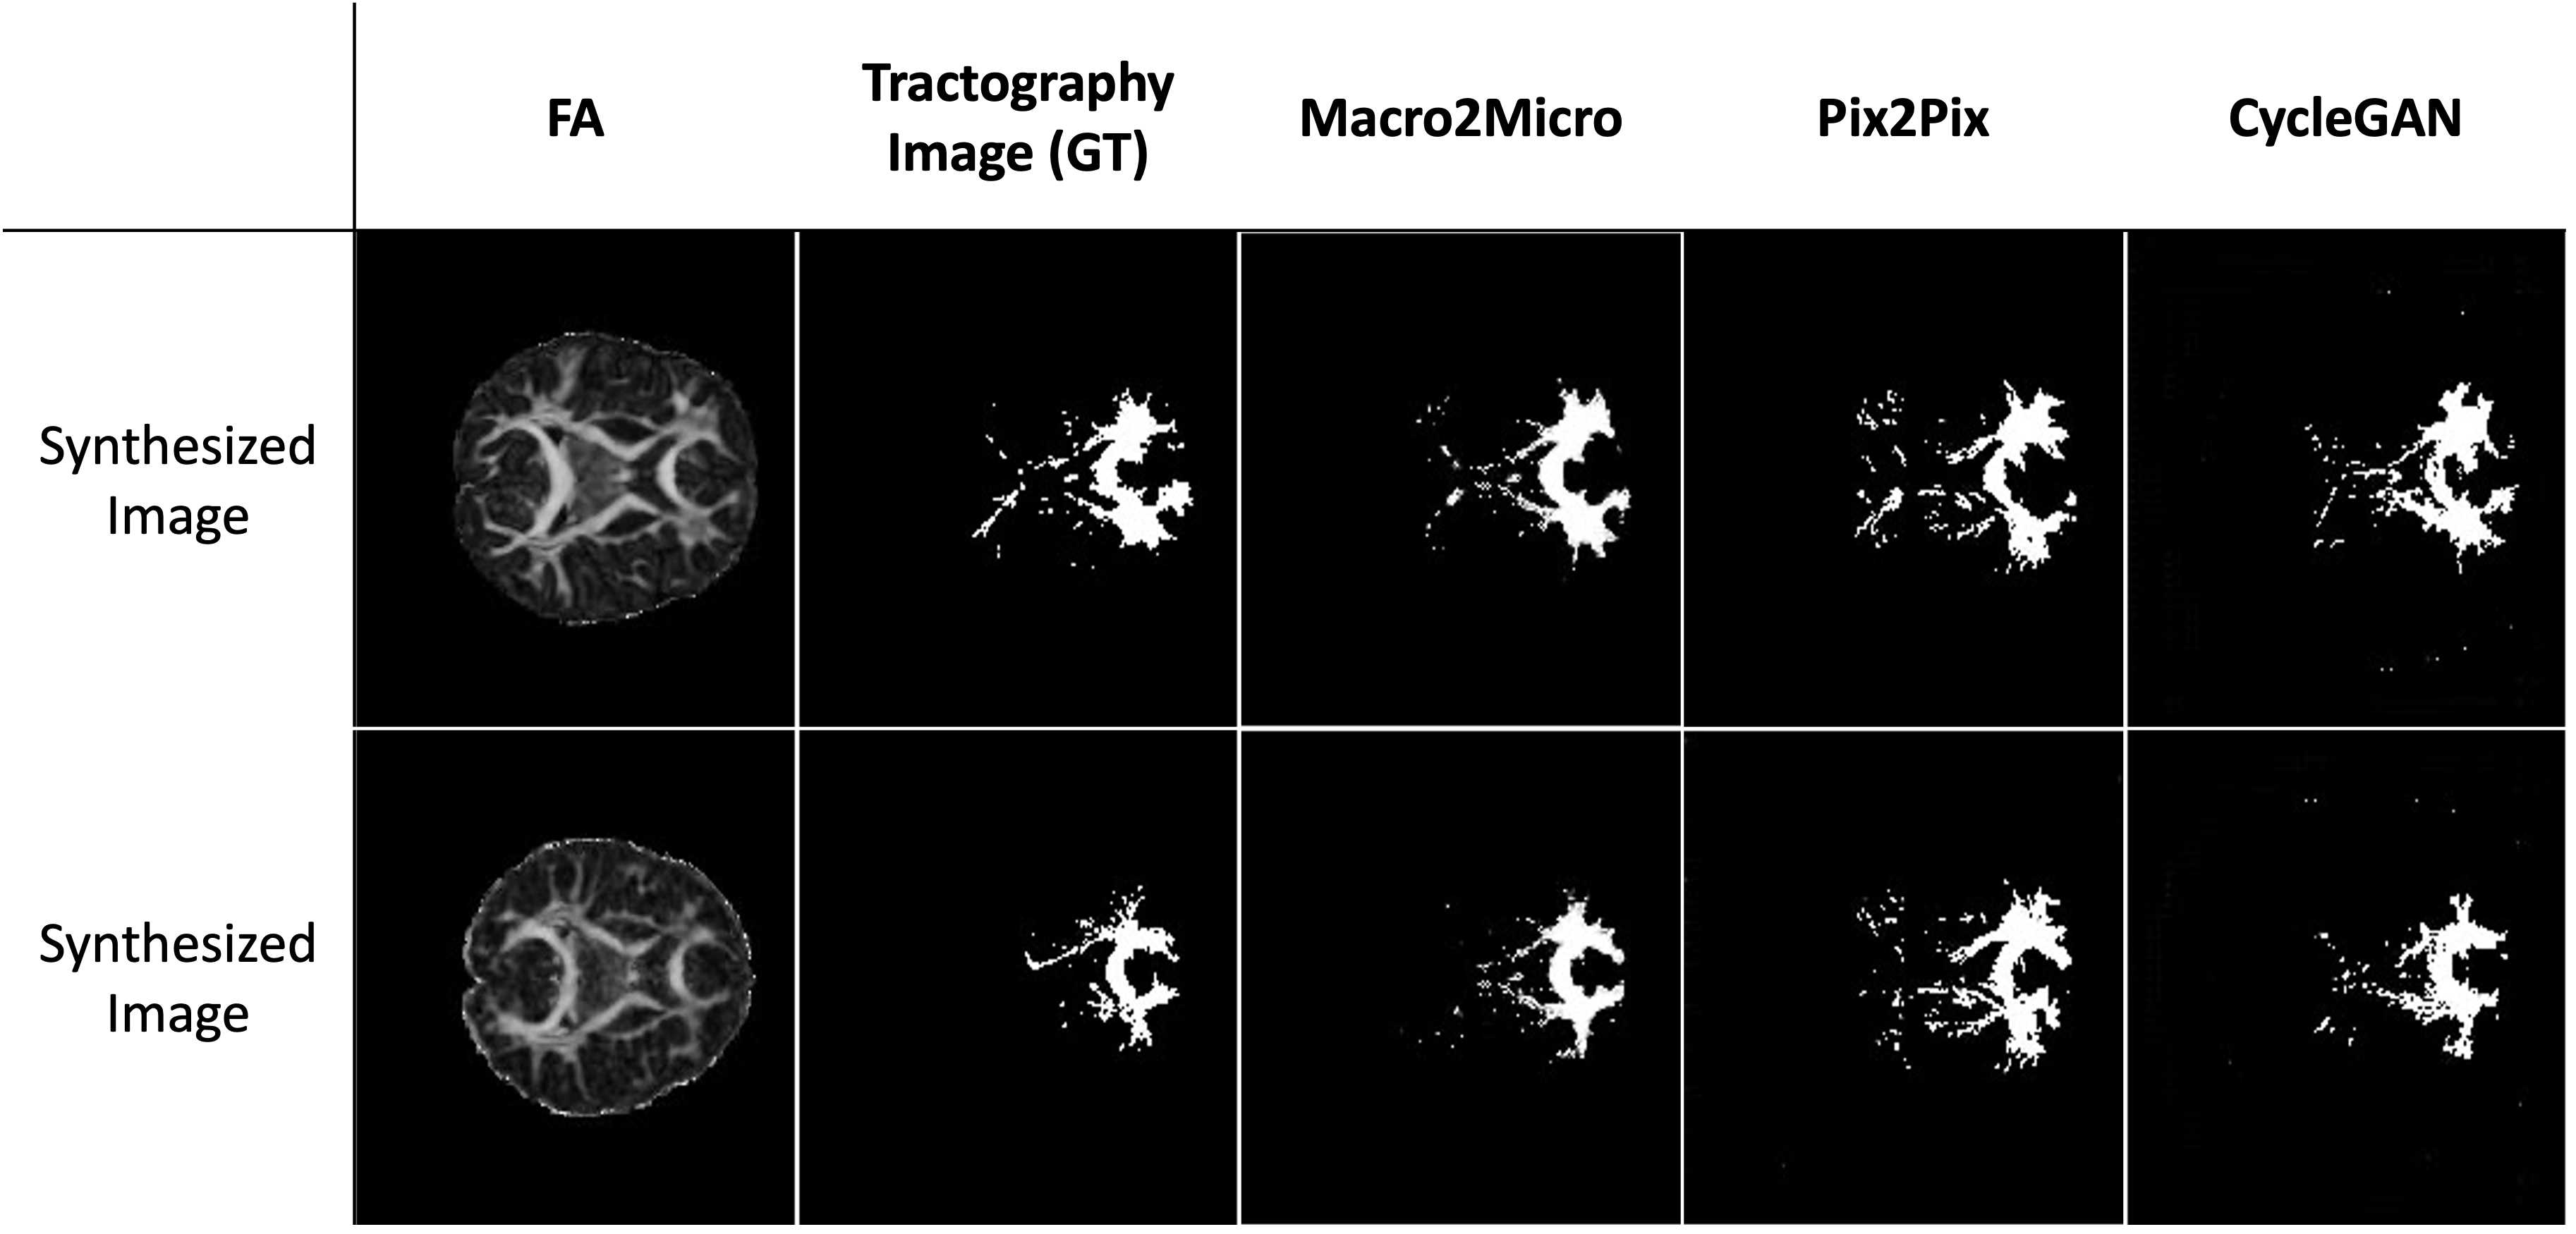

FA Image Translation to Tractography. Our model’s results were most comparable to the ground truth tractography. In Figure 7, the overall position of the fiber passing through the vmPFC region and the dense region where many streamlines pass were well predicted. Our results exhibit less noise and achieve more accurate generation of target regions compared to Pix2Pix and CycleGAN, which tend to yield noisier results around the target tractography. Additionally, our results demonstrate state-of-the-art performance in terms of SSIM, PSNR, MAE, and MSE scores, as shown in Table 4.

Refer to caption

Figure 7: Qualitative comparison of generated 2D Tractography from FA images.

Macro2Micro 0.8551 17.0572 0.0521 0.0474